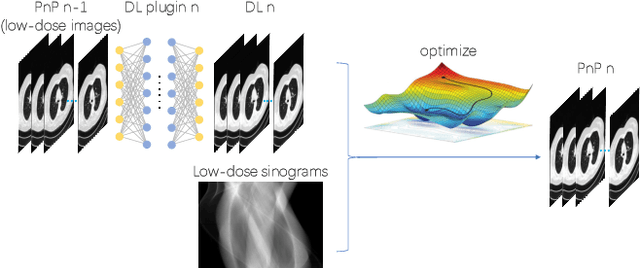

The Plug-and-Play (PnP) framework was recently introduced for low-dose CT reconstruction to leverage the interpretability and the flexibility of model-based methods to incorporate various plugins, such as trained deep learning (DL) neural networks. However, the benefits of PnP vs. state-of-the-art DL methods have not been clearly demonstrated. In this work, we proposed an improved PnP framework to address the previous limitations and develop clinical-relevant segmentation metrics for quantitative result assessment. Compared with the DL alone methods, our proposed PnP framework was slightly inferior in MSE and PSNR. However, the power spectrum of the resulting images better matched that of full-dose images than that of DL denoised images. The resulting images supported higher accuracy in airway segmentation than DL denoised images for all the ten patients in the test set, more substantially on the airways with a cross-section smaller than 0.61cm$^2$, and outperformed the DL denoised images for 45 out of 50 lung lobes in lobar segmentation. Our PnP method proved to be significantly better at preserving the image texture, which translated to task-specific benefits in automated structure segmentation and detection.